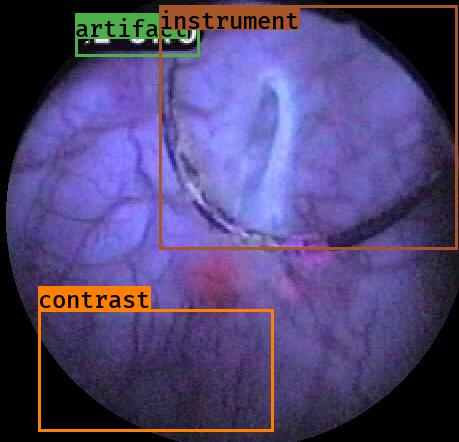

Examples for bounding box annotations for detection are shown in Fig. 2. It can be observed that while multiple boxes are annotated for several small specular areas; contrast, blur and instrument have relatively larger areas. Due to the overlap between two or more classes, the annotation by experts varied. This was minimized by following the detailed annotation protocol above. For semantic segmentation, a larger area mask was preferentially used to delineate locally very cluttered small specularity artifacts (see Fig. 3).

For semantic segmentation, we released 475 annotated frames for 5 different classes that include specularity, saturation, artifact, bubbles and instrument. For test data, 122 frames were annotated for online evaluation of participants algorithm. All data are available online at [3].

Generalization